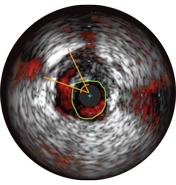

IVUS can help clarify degree and type of stenosis (i.e, MLA, plaque burden, and calcium). While IVUS can also characterize plaque rupture, thrombus, and dissection, calcium may be more common in everyday PCI. An important factor in your stenting strategy, calcium is characterized by very bright areas with acoustic shadowing that blocks out the image behind. Reverberations may also be seen.

Malapposition is identified by blood behind the stent struts. ChromaFlo imaging colors blood flow red for easy recognition of malapposition and other lumen features.